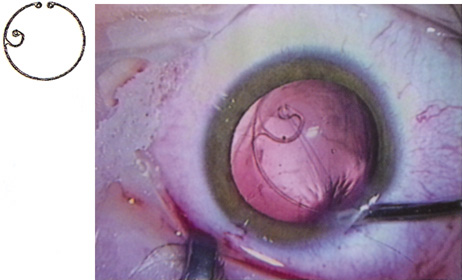

Although slit-lamp examination can give the ophthalmologist an excellent estimate of endothelial health, sometimes a formal assessment of the corneal endothelial cell density is helpful (Fig. 4). This information is most likely to be helpful in advising patients who may be at greater risk of postoperative corneal decompensation. Specifically, patients with cornea guttata, previous ocular surgery, history of blunt ocular injury,56 exfoliation syndrome,57 iridocorneal-endothelial syndromes,58 or a history of glaucoma59 are known to have reduced endothelial cell counts. Patients with a history of acute angle closure are at particular risk because each episode of elevated intraocular pressure can damage endothelial cells.60

There are qualitative and quantitative methods for endothelial cell evaluation. Cell density can be measured directly with an endothelial cell camera. The surgeon also should view the photograph and qualitatively estimate the regularity of the endothelial cell mosaic. Some instruments calculate a coefficient of variability and percent of hexagonal cells.

When an endothelial cell camera is not available, qualitative assessment of count and cell morphology can be accomplished at the slit-lamp using a technique called specular reflection.61 The ophthalmologist focuses a narrow parallelepiped on the corneal epithelium, directing the beam at the periapical cornea from a 45-degree angle. The slit beam is moved slowly from side to side until the bright corneal reflex strikes the examiner's view from the epithelial surface reflection (first Purkinje-Sanson image). On high magnification, the examiner should focus on the endothelial surface just next to the bright reflex. The image of the endothelial mosaic will come into view. The surgeon can make a qualitative assessment of the cell density and degree of regularity. With practice, these estimates can be surprisingly accurate.